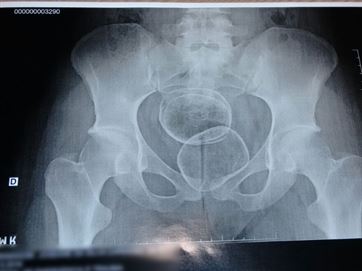

A droga foi descoberta quando passava pelo scanner corporal.Ela foi encaminhada ao Hospital de Emergência e Trauma Senador Humberto Lucena, onde passou por exames para retirada da droga.